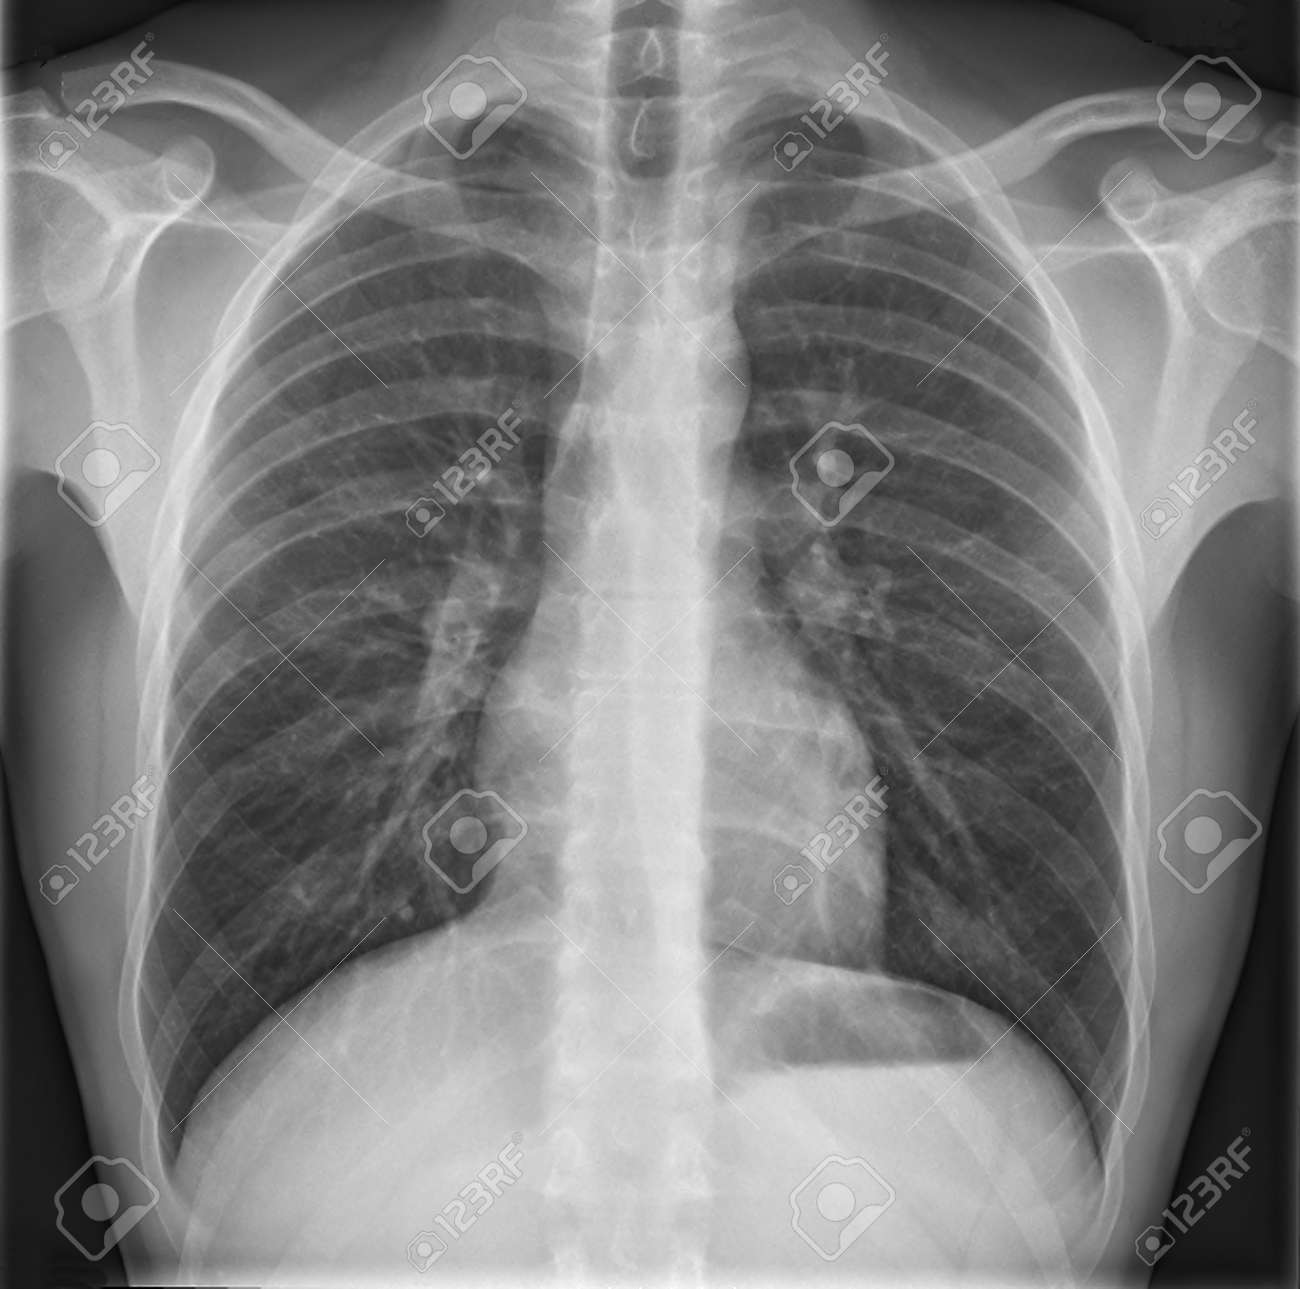

レントゲン 白い部分- X線が通過しにくい場所は白く、通過しやすい場所は黒くなります。 ですから、骨や心臓などX線が通過しにくい場所は白く、 肺(空気)や皮膚、筋肉など通過しやすい場所は黒くなります。 以上の事から、 >レントゲン写真って、白い部分が物体?また、厚みによってもエックス線の通過する量は変化します。 薄いものほど黒く、厚いものほど白く写ります。 骨や肺(空気)はエックス線吸収率が他の臓器と大きく異なるので画像のコントラストを得やすいのですが、筋、脂肪、充実性臓器、液体などはエックス線吸収率が近く、コントラストが得られにくいのです。 それを画像化するために、少しでも

肺野の含気過多があり細気管支炎様のレントゲン像だが、同時に上縦隔右気管支上の部分が反対側の左と比べてやや白く透過性が悪くなっている。 このような場合気管支S1もしくはS2の浸潤影初期のことがある。 5日後に確認したレントゲン像を下に提示する。 右S1・2に均等影をみとめる。 肺気腫様の肺野に目を奪われるが、胸骨柄の輪郭が良く撮影されていて胸鎖 ① 初期のレントゲン検査では異常ありません。 ②痛みが持続する為、後日mri検査。 他の骨に比べると第2中足骨が白くなっています。 これは疲労骨折のサインです。 ③発症50日目。再度レ CTの色の違いとは? 白と黒の写り方の違いについてご説明します。 X線の吸収がいいものは白く写り、逆に透過してしまうものは黒く写ります。 例えば骨は硬くX線が通りにくく吸収しやすいため白く写ります。 白くなっている部分はX線を吸収しているため、高吸収域といいます。 逆に黒く映る場合はどのような場合でしょうか。 黒く映る場合はX線が吸収されず

1年後のレントゲン写真がこれ。 根尖周囲の黒く抜けている部分が 無くなりました。 歯のぐらつきもなくなりました。 根管治療(神経の治療)をすることなく 改善してきました。 1年前の時点で、 根管治療や抜歯を していなくて良かったです。胸のレントゲン写真を撮り、胸部の臓器の形や病変をチェックする胸部x線検査は、こうした病気の発見に大いに役立つ検査です。 見ている部位は同じでも、注目するポイントは違います。 白い影の中に黒く抜けた空洞が見える場合もあります。